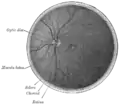

Diagram of the blood vessels of the eye, as seen in a horizontal section. (Central retinal vein not labeled, but region is visible. The central retinal vein is at bottom running away from the retina through the optic nerve.)